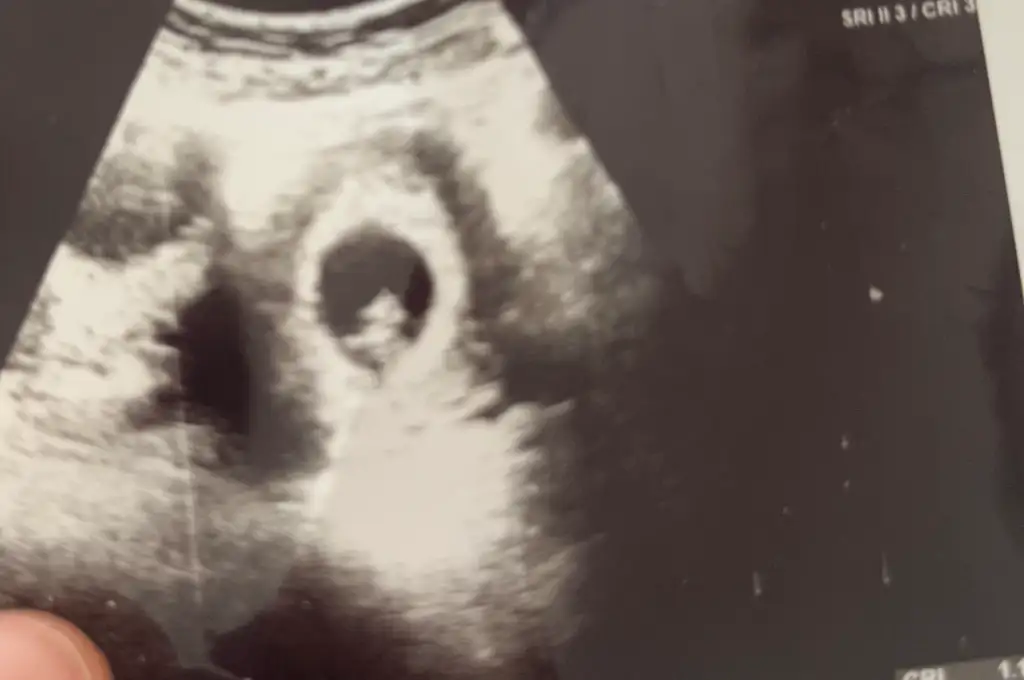

Dün doktorum klinikte değildi bugün gittim Elhamdülillah bebeğim benimle gördüm minigimi kalp atışlarını da gördük kanama alanı yok herşey yolunda çok şükür 🥲Hayatımda duyduğum en güzel melodiydi o kalp sesi o kadar duygulandım ki 🥺🥺🥺

Yaş:30

Sat: 16 Mayıs

Kese 5+4

Kalp atışı 7+0

İlk gebelik

Tahmini doğum :20 Şubat

Maşallah :D Biz kısayız 😅 Acaba olay ne ya dndj Birde cinsiyet tahmini alabilir miyim

Eklentiler

• 7C5D1AA8-3384-46E8-BED7-B8DB6D8D3735.webp